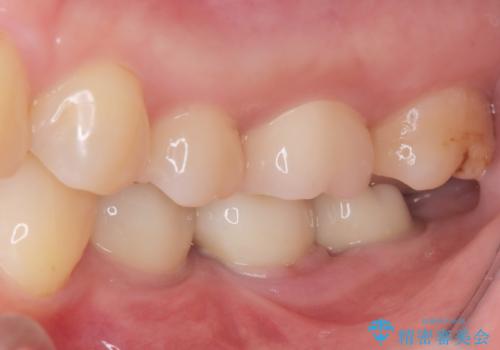

今回の治療では、虫歯の大きさや深さに応じて、異なるセラミック修復法を適用しました。

比較的軽度な虫歯には、セラミックインレー(詰め物)で対応し、健全な歯質を最大限に残しました。

進行した虫歯や歯の強度が低下している歯には、セラミッククラウン(被せ物)を選択し、歯全体を保護することで破折を防ぎました。

短期間での治療を可能にしつつ、天然歯と見分けがつかない審美性と、長期的に安定する機能性を兼ね備えたセラミック修復を実現しました。